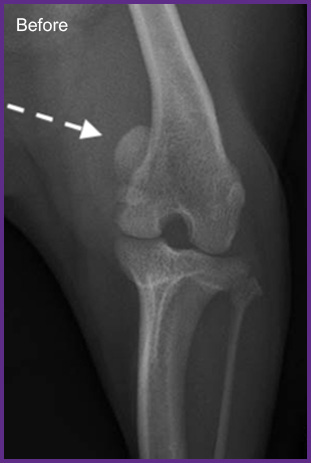

我們提供留院服務並擁有相應的治療設施,亦是小數備有CT電腦掃描及MRI磁力共振等大型醫療儀器的診所及醫院。